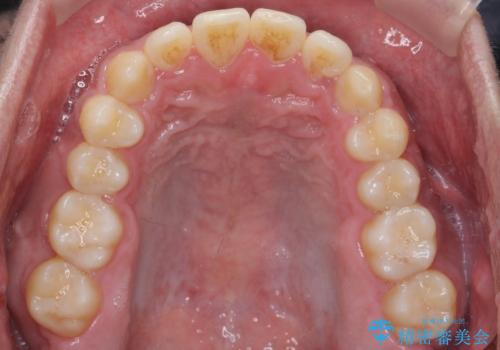

- 受け口を主訴に来院。

前歯のかみ合わせが逆になり上の前歯が奥に入っていました。

骨格性の受け口だったため、矯正用のミニスクリューを用いて、下の前歯をしっかり内側に入れました。

前歯を前に乗り越えさせるのは、ワイヤー矯正が一番早く歯に負担がかかりにくいです。

また、下顎はミニスクリューからマウスピースにゴムをかけて、下の歯並びが前に出ないようにして並べています。